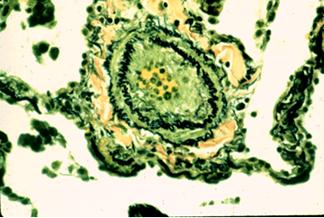

Arteriopatie pulmonara cu remodelare a peretilor arteriali pulmonari avind trei subtipuri:

hipertrofie simpla a mediei arteriale (forma general prezenta, precoce si potential reversibila)

arteriopatie pulmonara plexogenica cu hipertrofie a mediei, fibroza intimala si leziuni ale intregului perete arterial (forma avansata si ireversibila)

arteriopatie pulmonara trombotica cu hipertrofie a mediei si fibroza excentrica nonlaminara a intimei (determinata secundar de trombozele locale)

Microtromboze in situ

Aspect histologic arteriolar de HTP primara Leziuni plexiforme intr-un caz de HTP primara